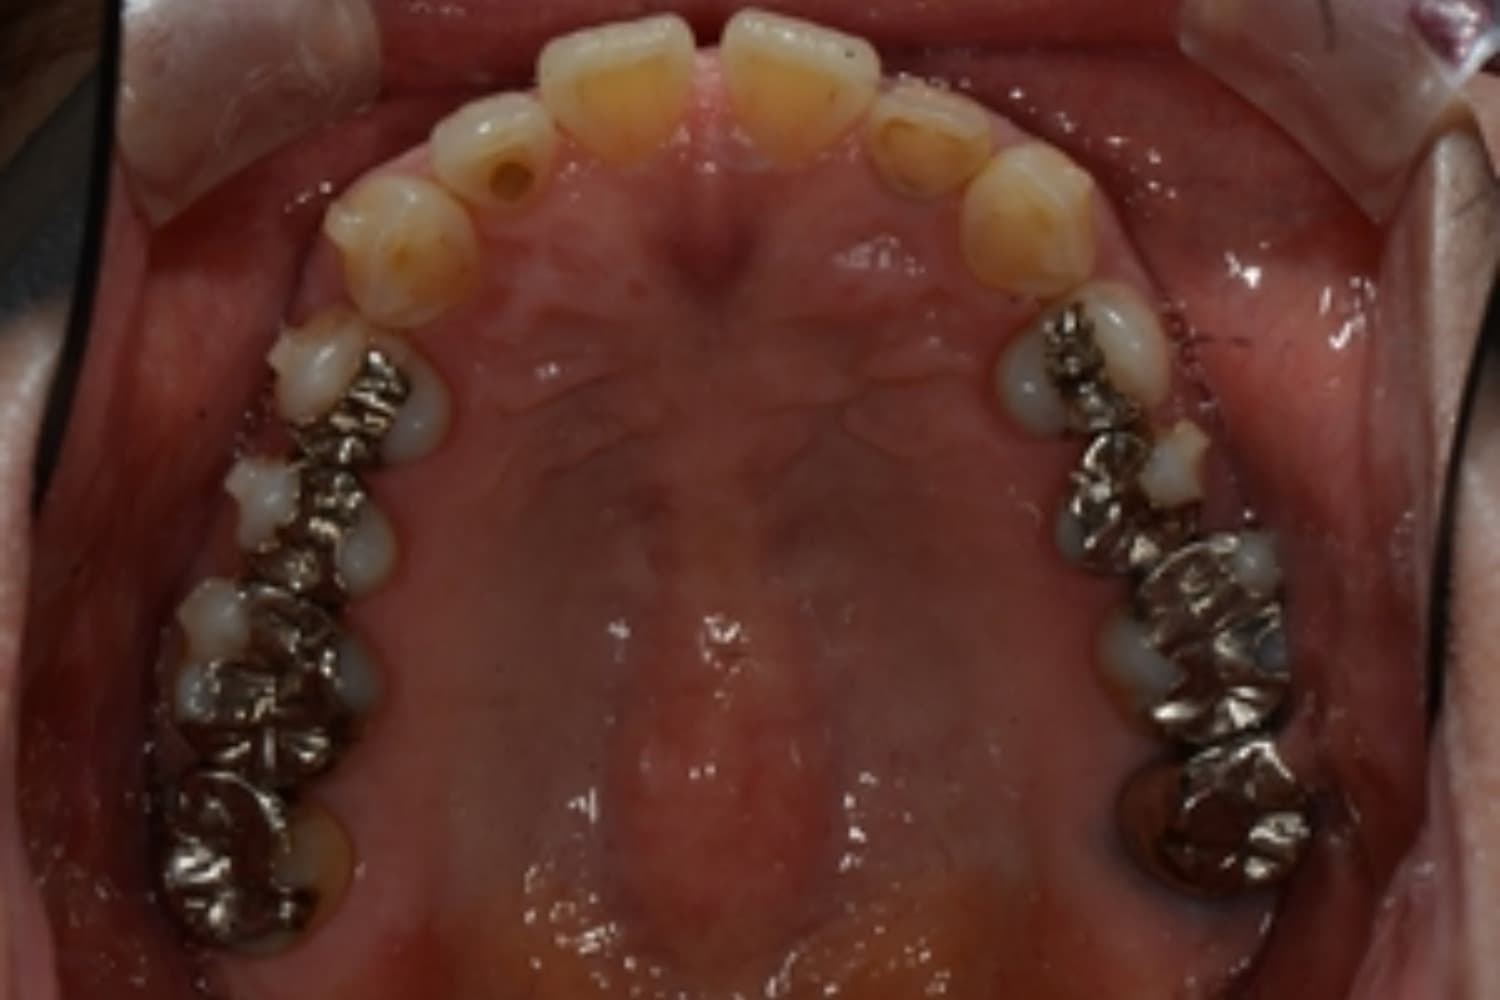

下顎大臼歯3本欠損症例

Before

After

左下第一大臼歯は保存が困難な状態であったため抜歯をおこないました。あわせて、ご来院時から欠損していた右下第一・第二大臼歯も含め、欠損部の補綴方法についてご説明し、インプラント治療を選択されました。

年齢

60歳

性別

男性

主訴

左下の第一大臼歯は別の医院で治療中でしたが、治療が思うように進まず、加えて他の箇所にも痛みが続いたことから、当院にご相談いただきました。

治療期間

10ヵ月

費用

140万円

副作用・リスク

インプラント治療は外科的な処置を伴い、多少の腫れや痛みが出ることがあります。 多くの場合は鎮痛薬で和らげることができます。